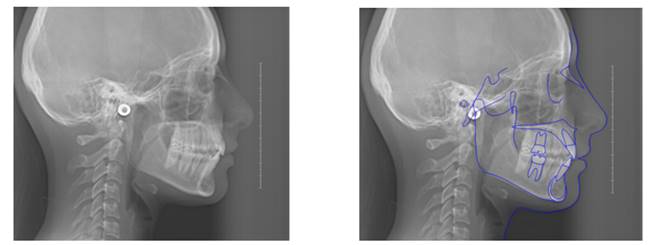

Methods: The clinical examination included extra-oral and intra-oral photographs, panoramic radiographic, lateral cephalometric, stone casts, and upper and lower arch analysis obtained from ClinCheck 3.0.The treatment planning was resolved the crowding in both upper and lower arches and the severe rotation of 33 tooth (46°) using Invisalign system as well as the canine and molar relationship, dental verticalization, adequate over jet, overbite and dental midline using the same system. The duration of the treatment was approximately eight months.

Results: In Post-treatment extra oralphotographs, no significant changes were observed at the end of the treatment. Intraoral photographs showed an important and notable improved aesthetics. The canine relationship improved slightly and molar Class Irelationship was maintained. An increase in transverse diameter was observed at the level of first premolars, second premolars and first molars. The overbite was improved. The crowding and the severe canine rotation were corrected. No obvious root resorption was radiographically evident and slight cephalometric changes.